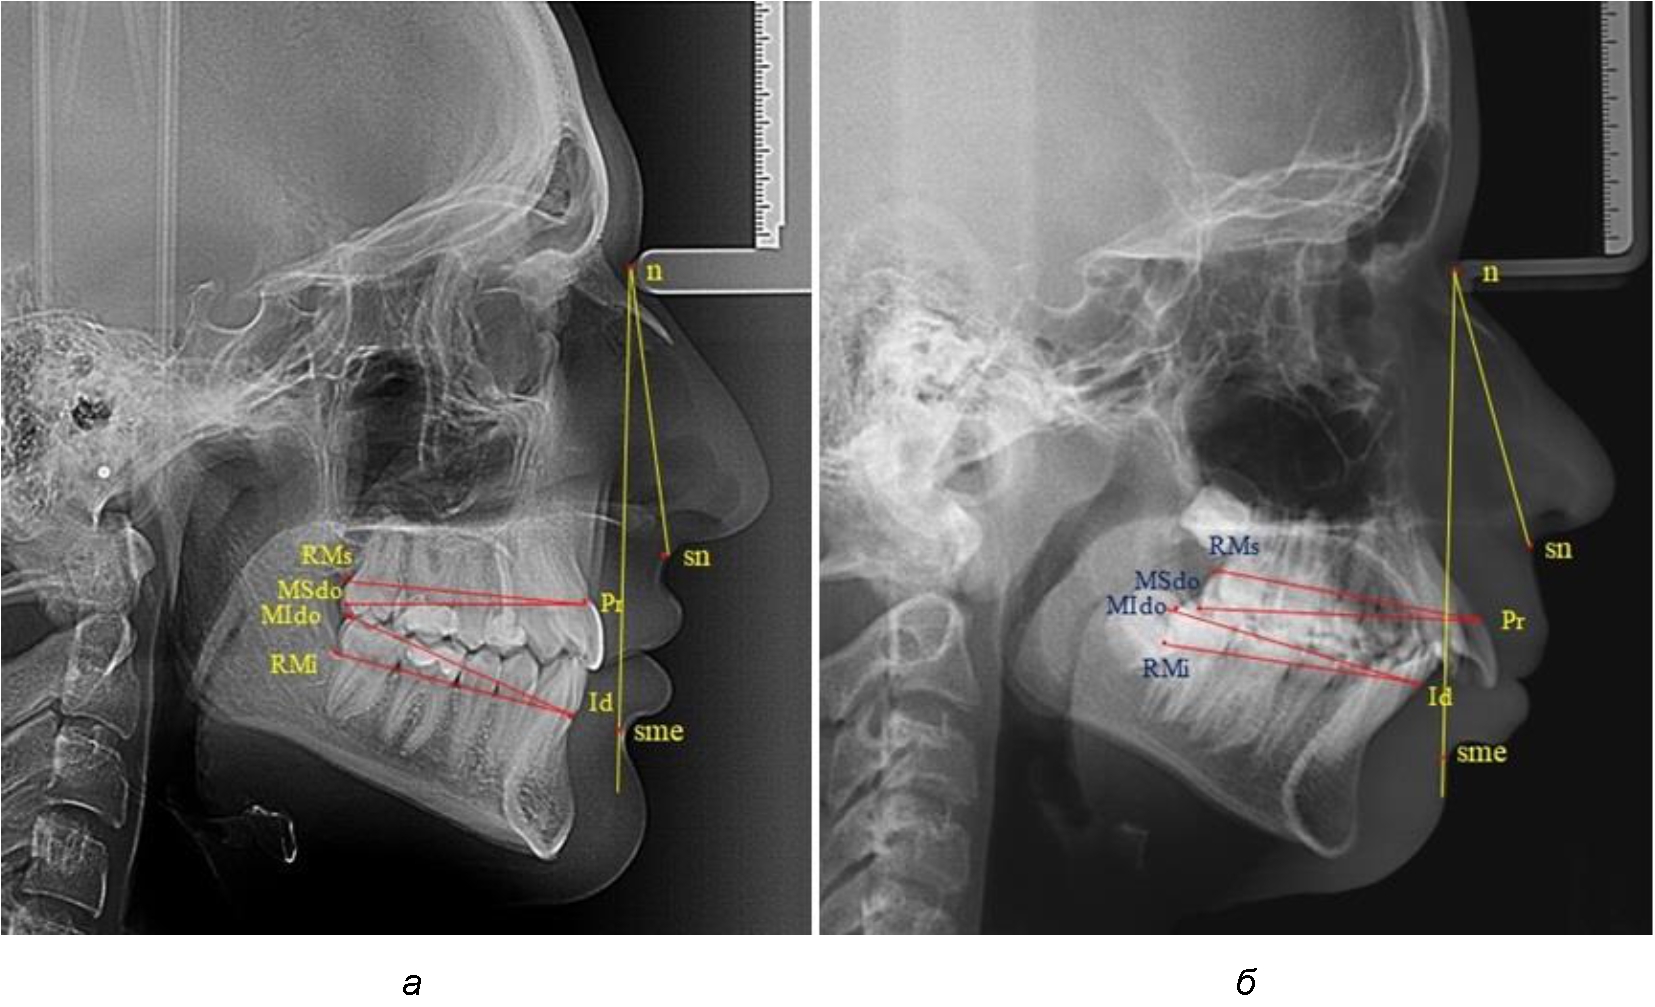

Измеряли межальвеолярное расстояние на верхней челюсти (Pr-RMs) и на нижней челюсти (Id-RMs) и сравнивали показатели между собой. Альвеолярно-окклюзионный размер на верхней челюсти (Pr-MSdo) сравнивали с аналогичным параметром нижней челюсти (Id-MIdo). При анализе 32 телерентгенограмм с дистальной окклюзией использовали те же ориентиры (рис. 1).

Рис. 1. Точки и линии телерентгенграмм при физиологической (а) и дистальной (б) окклюзии

При физиологических вариантах прикуса дистальные окклюзионные точки моляров, как правило, располагались практически рядом, в то время как при дистальном соотношении нижние моляры анализируемый окклюзионные точки, как правило, располагались позади верхних.

При сравнительном анализе носовой части угол составлял 28°, для которого соразмерность с гнатической частью составляла 17,3° (28/1,618 = 17,3°), в то время как в анализируемом случае угол значительно превышал расчетную величину и был 26°. Назально-супраментальный угол составлял 20°, что характерно для гнатической формы дистальной окклюзии. При анализе размеров верхней челюсти размеры ее межальвеолярного и альвеолярно-окклюзионного расстояний были на 4–5 мм меньше размеров нижней челюсти. В данном случае укорочение размеров верхней челюсти и увеличение тела, подбородка и угла нижней челюсти предполагало комплексную (ортодонтическую и хирургическую) реабилитацию пациента (рис. 2).

Рис. 2. Анализ фотоснимка (а) и рентгенограммы (б) при гнатической форме дистальной окклюзии